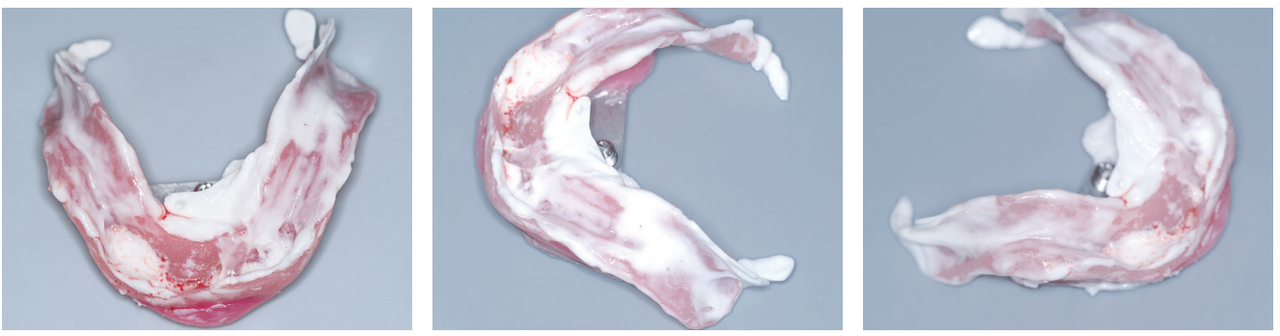

1) Alginate wash impression

알지네이트를 이용하여 인상채득을 하였다.

2) 모델 분석

상악 악제 상태는 매우 양호하다.

하악 악제는 구치부 부위 치조정 흡수가 너무 많이 진행되었다. 특히 좌측 구치부 치조정은 negative 상태이다. 전치부는 돌출이 심하다.

파노라마 사진과 모델 진단에서 Kelly’ combination syndrome 상태를 확인하였다. 이런 증례에서는 완성 틀니 장착 후 하악 구치부에서 지속적인 통증을 호소한다.

5) 상·하악 active functional impression

Gnathometer M이 부착된 tray를 이용해서 상악부터 실리콘 인상재를 이용하여 기능인상을 채득하였다.

이어서 하악도 기능인상을 채득하였다.